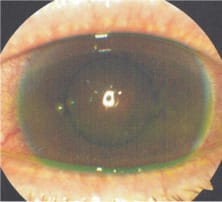

Figure 4 was taken about two weeks after completion of the anti-viral medications. The patient had worn the LDS lenses for about three hours before removal for this photograph.

Figure 4. Appearance of patient's cornea following two weeks of antiviral therapy. The lens had been worn for approximately three hours and removed for the photograph.